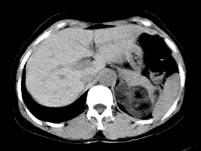

问题 男性,28岁,左腰背酸胀5个月,CT检查如图所示,应诊断为 ( )

选项 A、左肾上腺腺瘤 B、左肾上腺转移瘤 C、左肾上腺错构瘤 D、左肾上腺嗜铬细胞瘤 E、左肾上腺髓样脂肪瘤

答案 C